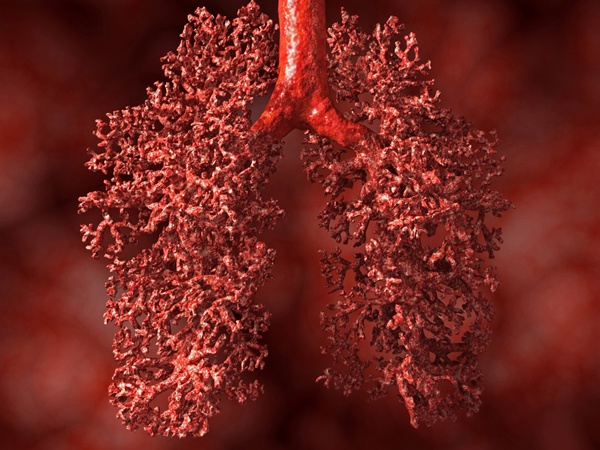

Phổi là cơ quan duy nhất trong cơ thể người có thể nổi trên mặt nước. Phổi ở người chứa khoảng 300 triệu cấu trúc giống như bong bóng được gọi là phế nang, giúp trao đổi carbon dioxide trong máu với oxy. Khi các phế nang chứa đầy không khí, phổi có thể nổi trên mặt nước. |